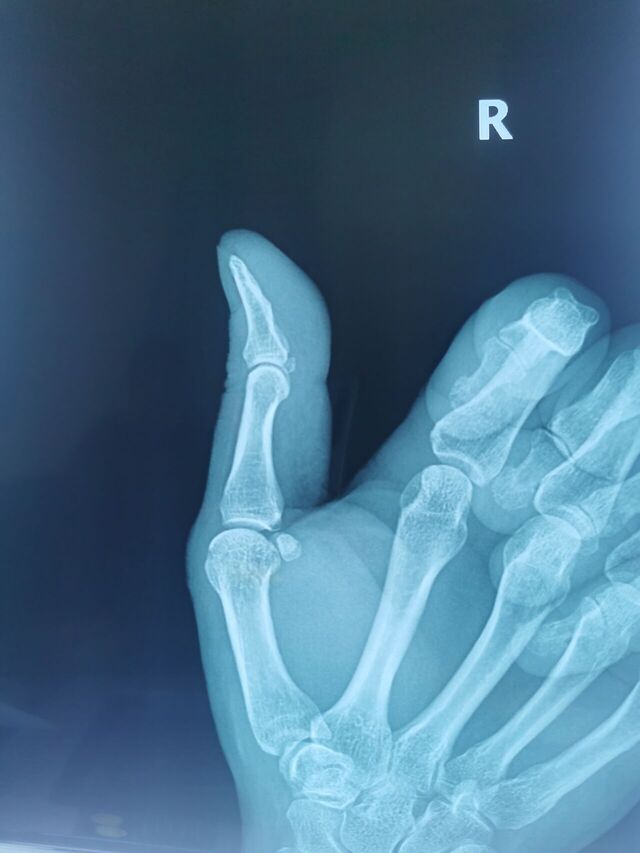

拇指掌指关节桡侧副韧带陈旧损伤

侧方应力试验(+)